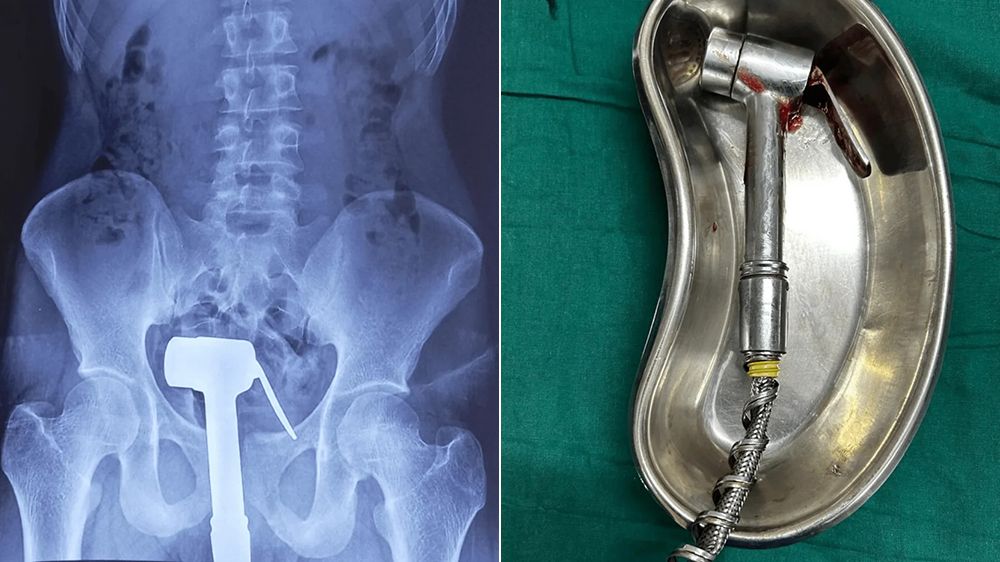

印度孟買格蘭特醫學院,去年1月8日發表一份探討智能障礙患者直腸異物插入病例的報告

,近來社群流傳的畫面就是其中的病例。當事人是一名23歲輕度智障男性患者,自己將手

持式淋浴器插入肛門,其中淋浴器完全進入體內,而水管的部分仍留在體外

醫師指出,患者就診是有疼痛和不適,承認這麼做是為了獲得性快感,在通過X光確認淋

浴器插入後沒有破損,體內骨骼等情況也都正常,於是為患者進行全身麻醉後,對他進行

肛門擴張後,醫護人員伸手進入按住淋浴器把手,成功把淋浴器取出。患者術後沒有出現

併發症,且出血量極少,留院觀察一夜後,將其轉介給精神科醫師進行評估。